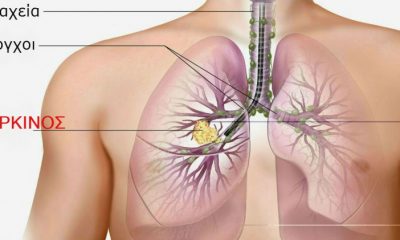

Kαπνίζετε; Τουλάχιστον αποτοξινωθείτε… Αυτές είναι οι 7 τροφές που καθαρίζουν τους πνεύμονες.

21 Σεπτεμβρίου 2018Αδιαμφισβήτητα οι πνεύμονες είναι από τα σημαντικότερα όργανα για τη λειτουργία του σώματος. Σε καθημερινή βάση...